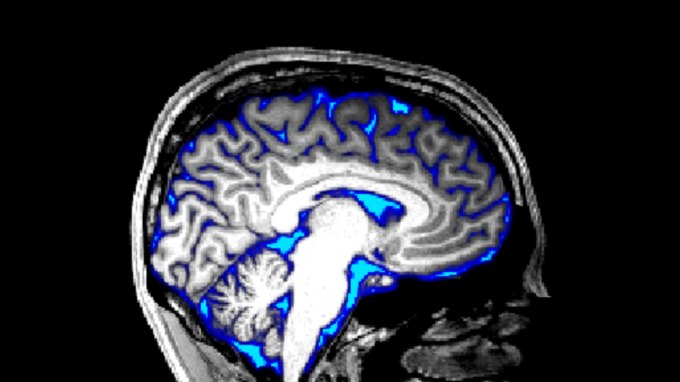

Scientists triggered the flow of spinal fluid in the awake brain

If future studies confirm these waking waves wash away toxic proteins from the brain, the finding could lead to new treatments for brain disorders.